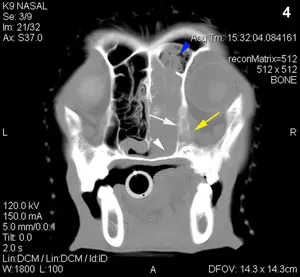

A 12-year-old spayed female English springer spaniel was presented for nasal discharge and intermittent epistaxis.

The dog was bright, alert, and hydrated, with a body weight of 19.6 kg. A hemorrhagic, mucoid discharge was noted coming from her right nostril (Figure 1). Airflow was absent from the right nostril. Her right eye retropulsed normally. Oral examination was unremarkable. Her submandibular lymph nodes were 0.5 cm in diameter. The rest of her physical examination, including blood pressure and temperature, was unremarkable.